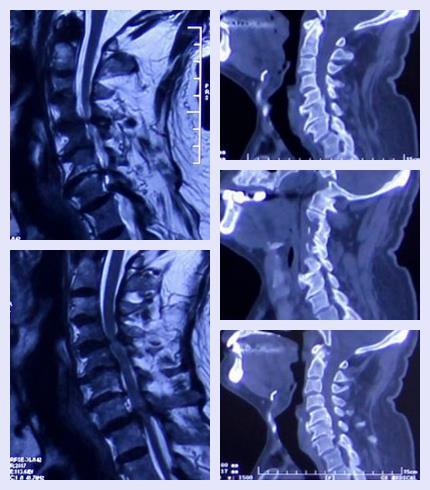

结合患者病史、体征等初步诊断为颈椎管狭窄。集合影像学检查确诊为颈椎管狭窄。

影像学